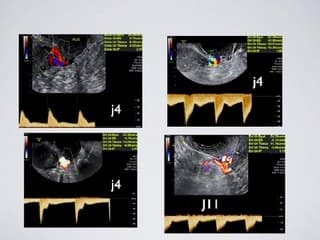

L'auteur pose la question de l'utilité du Doppler utérin dans le bilan de l'infertilité. La réalisation peut se faire au 4 eme puis 11 eme jour du cycle pour essayer de mieux apprécier la réceptivité endometriale et donc les chances d'implantation. Ses conclusions penchent vers l'intérêt de le réaliser au moment du déclenchement, afin de retarder le transfert ou de congeler les embryons en cas de mauvais paramètres ( IP et notch).